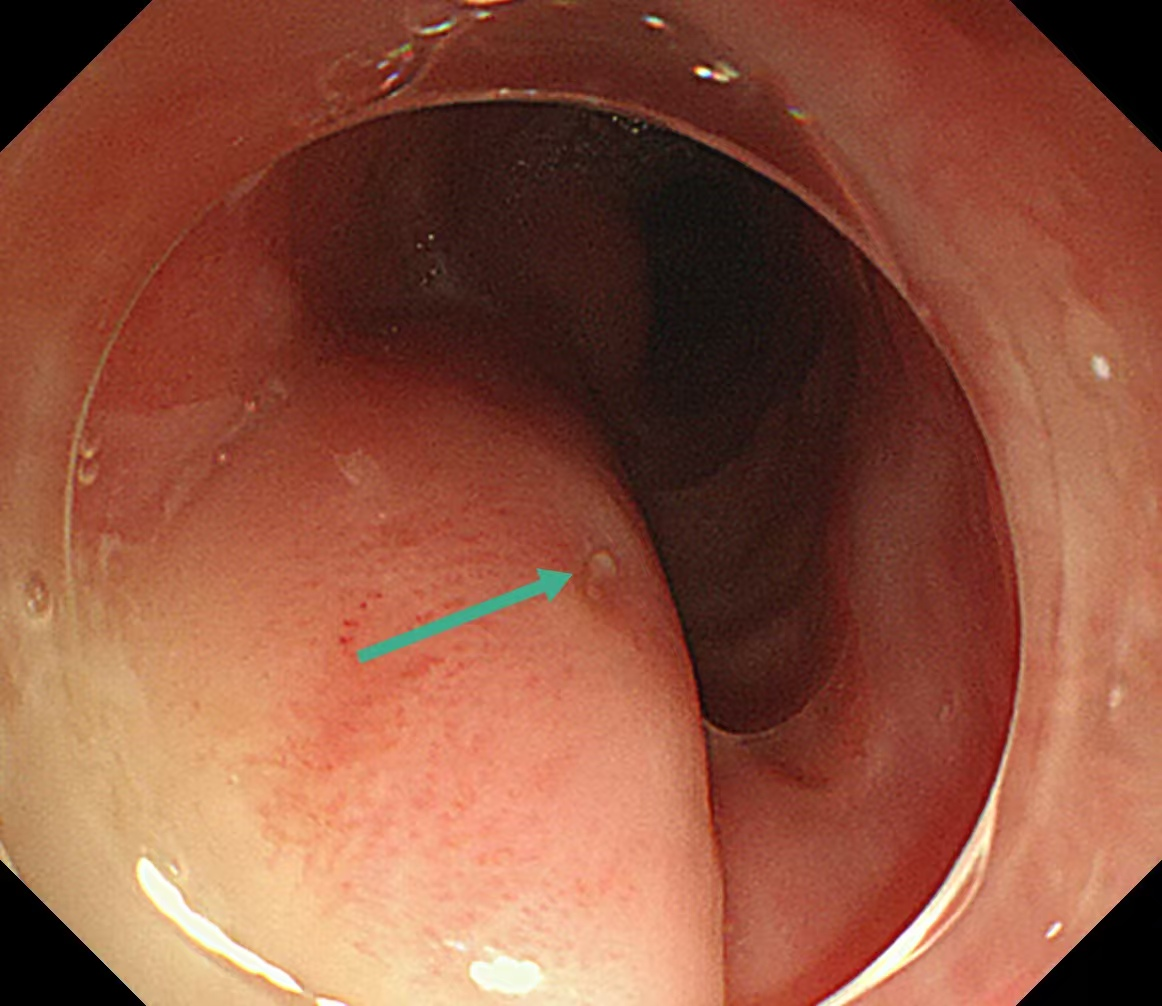

随着胃镜插入食管,刘蔚在患者食管入口处查见一脓肿,顶端有一开口样凹陷。轻轻按压,竟有脓液从一个细小的破口处不断冒出,结合CT报告和患者卡刺一周的病史,刘蔚立刻判断:这根鱼刺不是常规横卡在食管腔,应是由此处刺破了食管黏膜,钻进了食管壁的夹层中,在里面“潜伏”了整整一周,持续刺激食管壁,引发了严重的感染化脓,形成了脓肿。

食管入口查见一脓肿,顶端有一开口样凹陷,考虑异物由此处进入食管壁